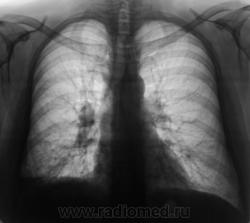

Пациент направлен на исследование ОГК с диагнозом пневмония.

не удивлюсь,если в мокроте обнаружат палочки Коха

Палочки-это еще ничего, а мне кажется, что здесь онкологию искать нужно.Дай бог мне ошибиться.

Снимок обзорный с разворотом. Впечатление пневмосклероза средней доли. Нечеткость правого купола диафрагмы. Что-то хочется латерографию и ТГ корней+боковая ТГ правого корня.

А почему пневмония в направлении? Что с клиникой?

Объективно, клиники пневмонии нет. По всей видимости, "пневмония", написана для проформы.